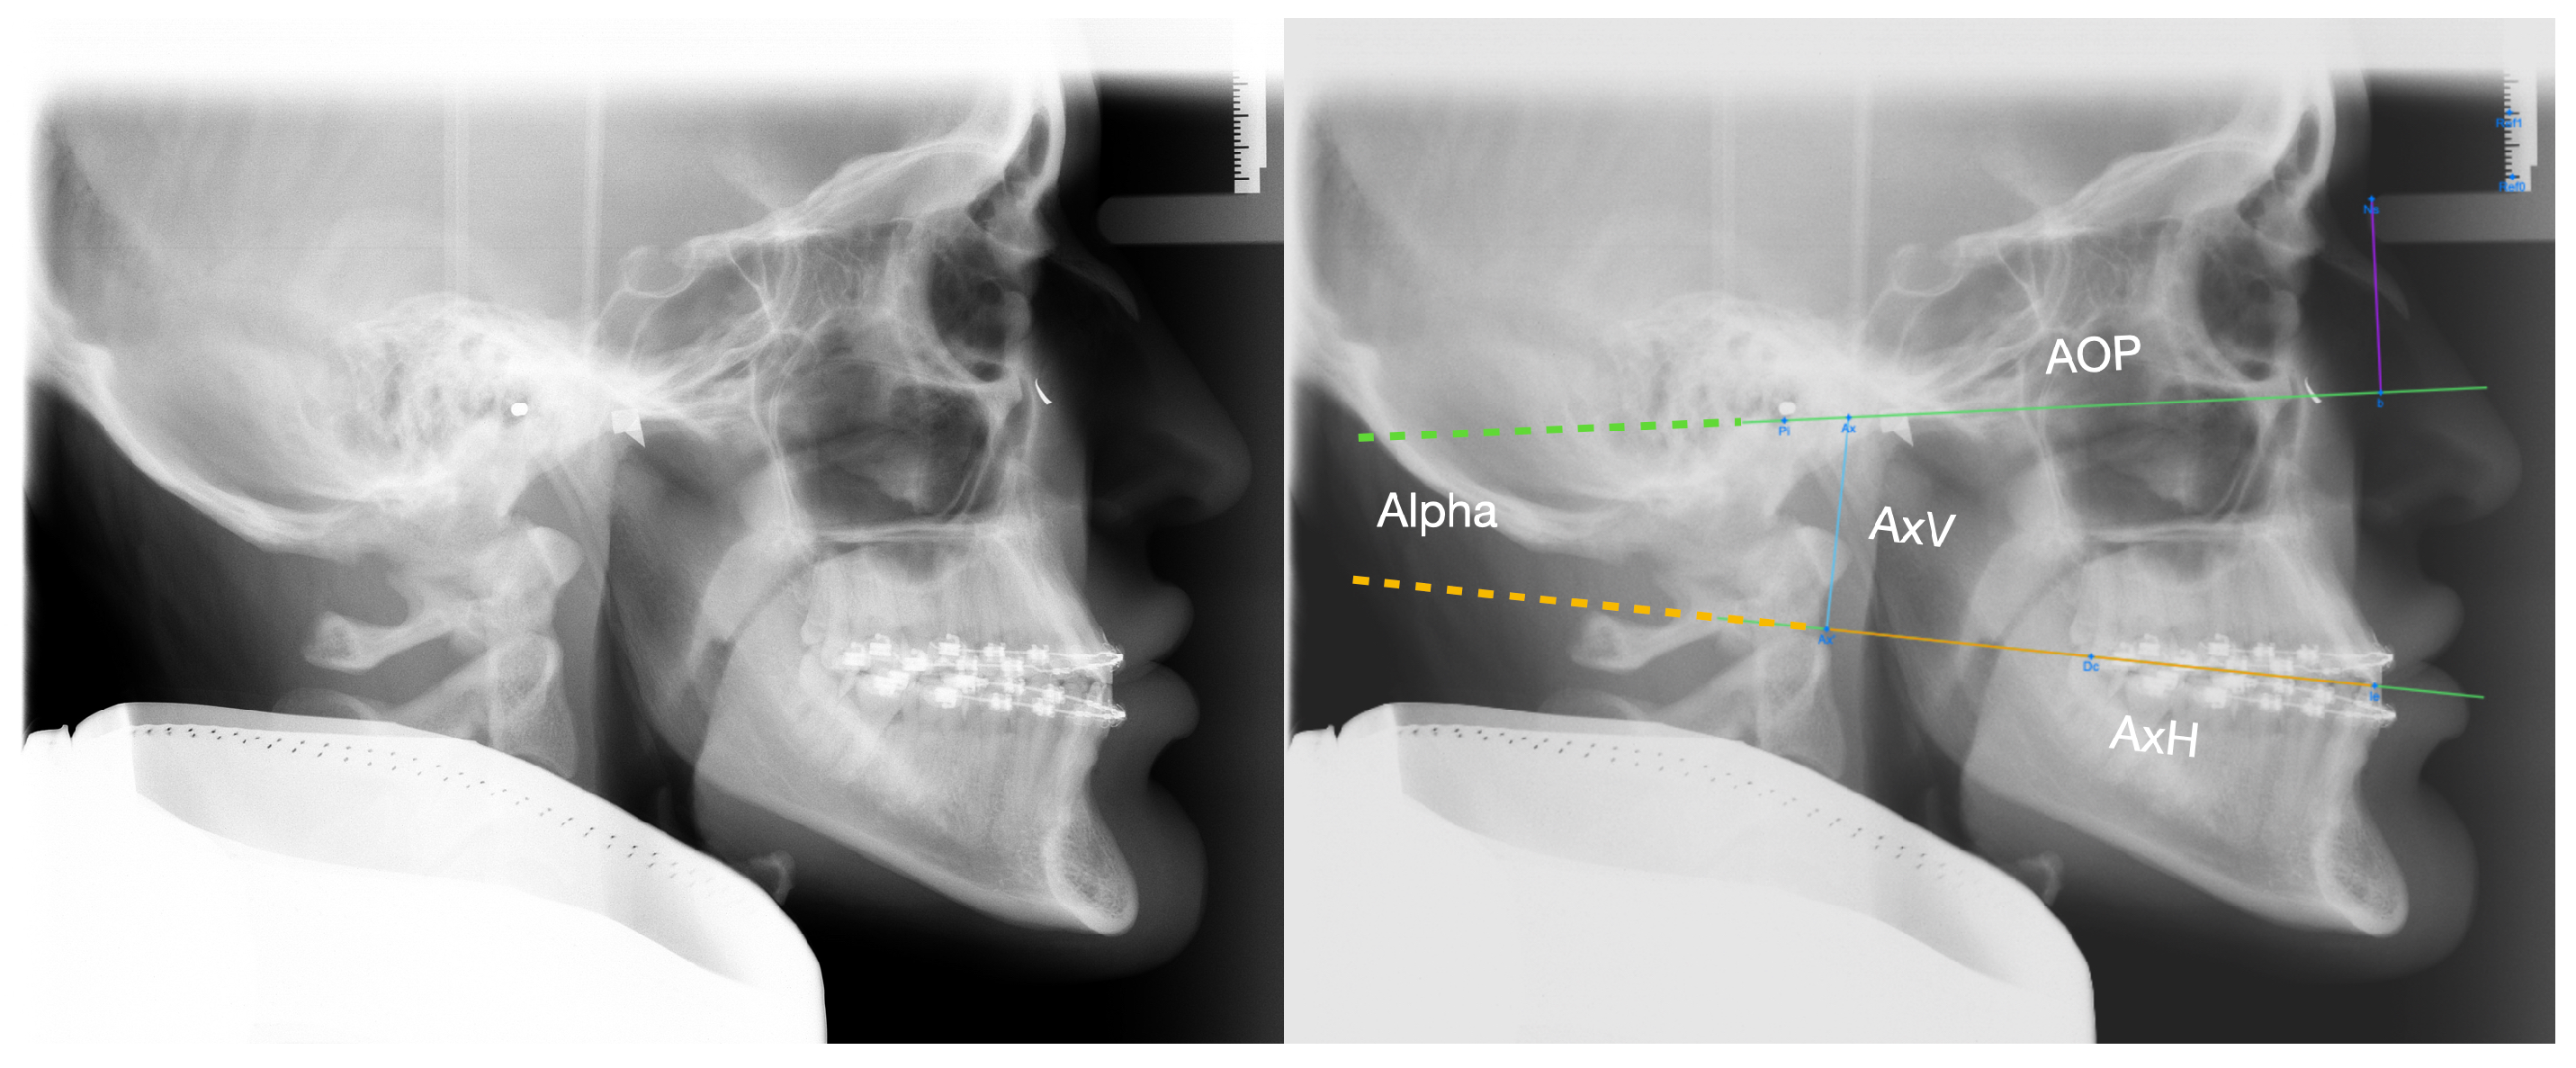

2. Materials and Methods

Statistical Analysis

3. Results